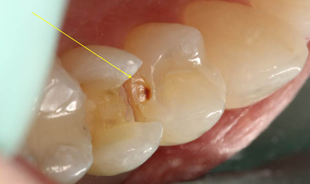

Based upon the patient’s history, compliance and desire to avoid costly dental treatment, a preventive treatment option was offered in an attempt to remineralize the interproximal lesions. The protocol involved an office fluoride varnish application with 3M ESPE Vanish Varnish and use of 3M ESPE Clinpro 5000 toothpaste at home. The areas were rescanned with The Canary System 6 months later with no reduction in the CN. Further review of risk factors revealed that the patient continued to consume one to two carbonated sugared drinks per day, which likely interfered with the remineralization process. Based upon the Canary findings, tooth #4 underwent restorative treatment. As soon as the mesial portion was opened, a large lesion was found which extended beyond the DEJ (Fig. 5a). Visual examination of the distal surface of tooth #5 revealed an area of brown decalcification with no obvious pathology (Fig. 5b). The distal surface of tooth #5 was opened (indicated with a yellow arrow) and a large lesion into the dentin was found (Fig. 5c).

Fig. 5c #5 distal lesion

The caries process in its earliest stage begins as a white spot lesion. The Canary System can detect changes in the tooth’s crystal structure, even at this early stage,13 allowing one to use a variety of treatment options including prevention, remineralization and conservative restorations. In this case, The Canary System provided a more accurate measurement of the interproximal lesions than the digital X-ray. The results of preventative treatment could be measured and ultimately led to a restorative outcome because of the patient’s diet. What appeared on radiograph to have not advanced through the DEJ, upon examination with The Canary System, indicated penetration of caries past the DEJ. This was subsequently confirmed by clinical exam during the restorative visit.